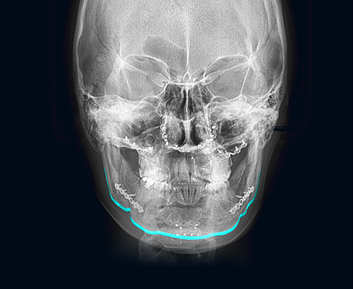

First of all, it is important to accurately analyze the shape of the cheekbones before surgery. It is necessary to consult with a clinician who has a lot of clinical experiences based on the results of X-ray and 3D-CT. At surgery, cheekbones are shaved based on the diagnosis. Depending on the skin elasticity of the person, an additional lifting procedure may also be recommended so the tissues are lifted together to give a lifting effect.

The facial bones do not grow after the growth period is over. In addition, cheekbone reduction surgery is a procedure in which the protruding cheekbone itself is moved inward and fixed to a new position, so you can rest assured that the cheekbones size will not increase again after surgery.

In case of cheekbone reduction surgery where your bone is completely cut, pins are needed to tightly fix the skin tissue and muscles and make them heal faster between the bones. This procedure equally happens with the other facial contouring surgeries too. Three months after the surgery, the bone is fully healed and firmly bonded as before the operation.